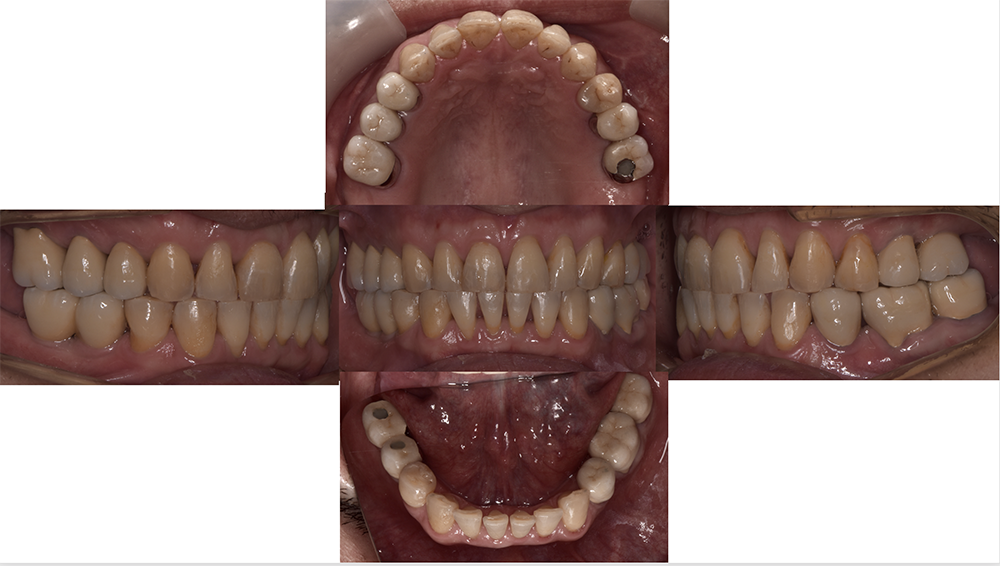

抜歯後は私の予測通り、長年治らなかった顎関節の症状が全く消失しました。つまり今までの顎の痛みの原因は、咬み合わせが原因という事になります。

原因がわかり理解出来れば歯が無い箇所はインプラント治療を行い、精密な虫歯治療の後にセラミック治療を行って正しい咬み合わせを構築しました。

T-Scanを使って咬み合わせの調整をしてすべての歯が均等に当たるように治療を致しました。この治療のように咬む力で問題が起こっている場合には、デジタル機器をきちんと用い、データを採りながら患者さんの咬んだ印象も参考にして治療を進めていくのは大切な事です。